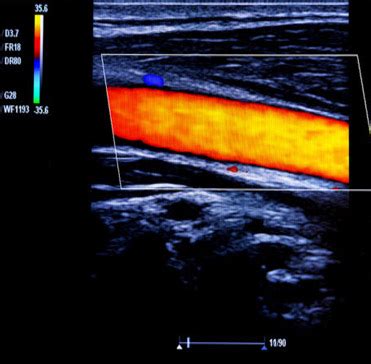

Now, let’s talk about the star of the show: how Doppler ultrasound specifically helps us spot Deep Vein Thrombosis (DVT). DVT occurs when a blood clot, usually in a deep vein of the legs, blocks blood flow. This is serious business, as the clot can break off and travel to the lungs, causing a pulmonary embolism (PE), which is a life-threatening condition. Doppler ultrasound is the gold standard for diagnosing DVT because it can directly visualize these clots and, crucially, assess the impact on blood flow. The procedure typically involves a trained sonographer applying a gel to your skin over the suspected area (usually the legs) and then moving a transducer, a handheld device, over the skin. This transducer emits high-frequency sound waves. As these waves travel through your body, they bounce off various tissues and structures, including your blood vessels and the red blood cells within them. The machine listens to the returning echoes. In areas without a clot, the sound waves will reflect off the moving blood cells predictably, showing a normal flow pattern. However, when a clot is present, it can partially or completely block the vein. This blockage will alter the sound wave reflections in several ways:

1. Direct Visualization of the Clot: In many cases, the clot itself can be seen as an echogenic (bright) material within the vein, obstructing the normal lumen (the open space where blood flows). The sonographer looks for a lack of compressibility of the vein; a healthy vein will flatten when gentle pressure is applied by the transducer, but a vein filled with a clot will remain rounded.

2. Altered Blood Flow Patterns: This is where the ‘Doppler’ part really shines. The machine detects changes in the frequency of the returning sound waves. If blood flow is reduced or absent in a segment of the vein due to a clot, the Doppler signals will be weaker or absent altogether. The sonographer will assess ‘phasicity’ (the normal rhythmic changes in blood flow related to breathing) and ‘compressibility’ of the veins. A clot disrupts these normal flow characteristics.

3. Augmentation and Reflux: The sonographer may also perform maneuvers like squeezing the calf muscle below the area of interest. Normally, this would cause a surge of blood flow towards the heart (augmentation). If a clot is present, this surge might be diminished or absent. They also look for ‘reflux,’ which is when blood flows backward in the vein after a period of compression, indicating faulty valves often associated with chronic venous issues or significant DVT.

By combining these findings—visualizing the clot, assessing compressibility, and analyzing the Doppler signals for flow abnormalities—doctors can confidently diagnose DVT. It’s a powerful tool because it provides real-time information about the health of your venous system, helping to guide treatment decisions and prevent serious complications.